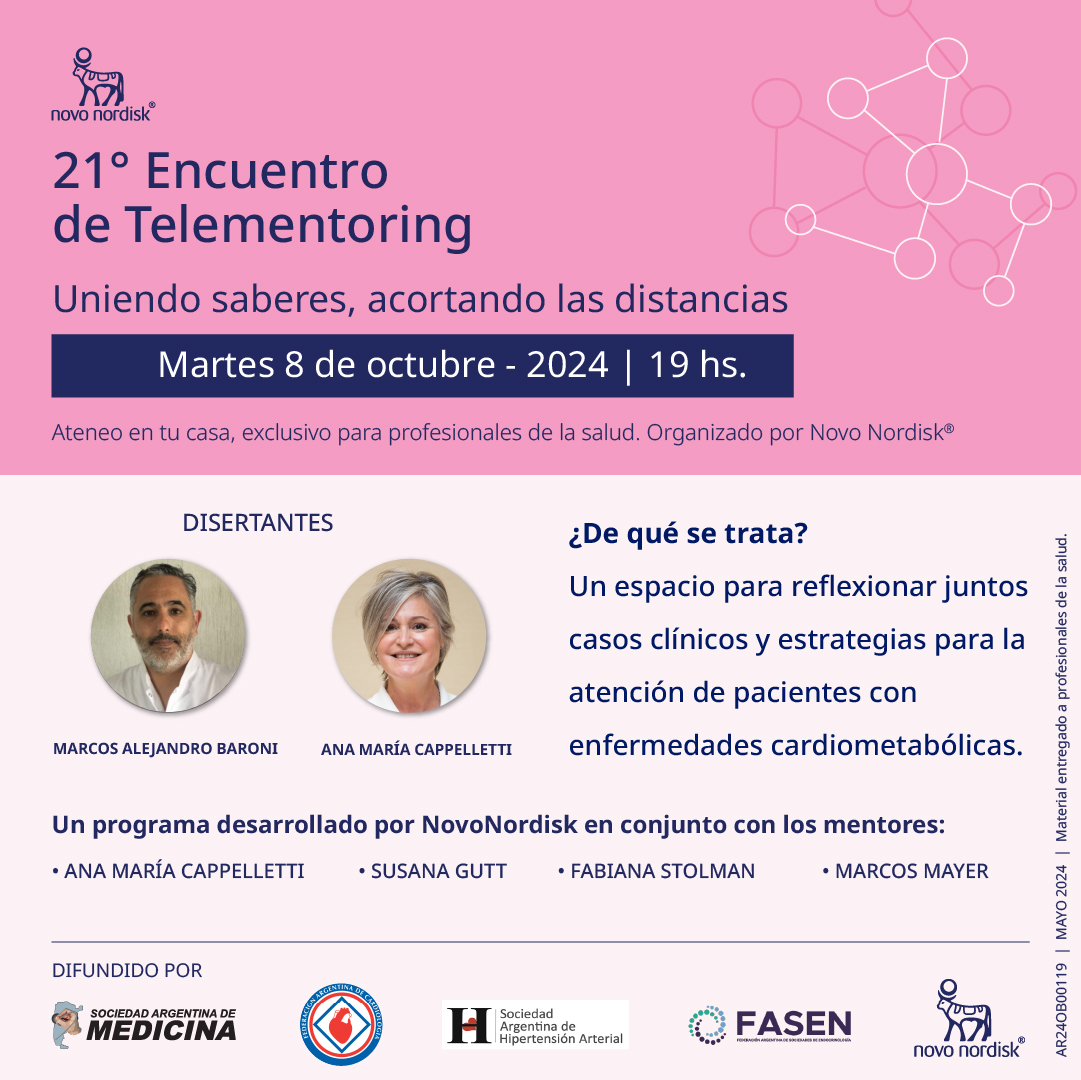

Auspicios FASEN